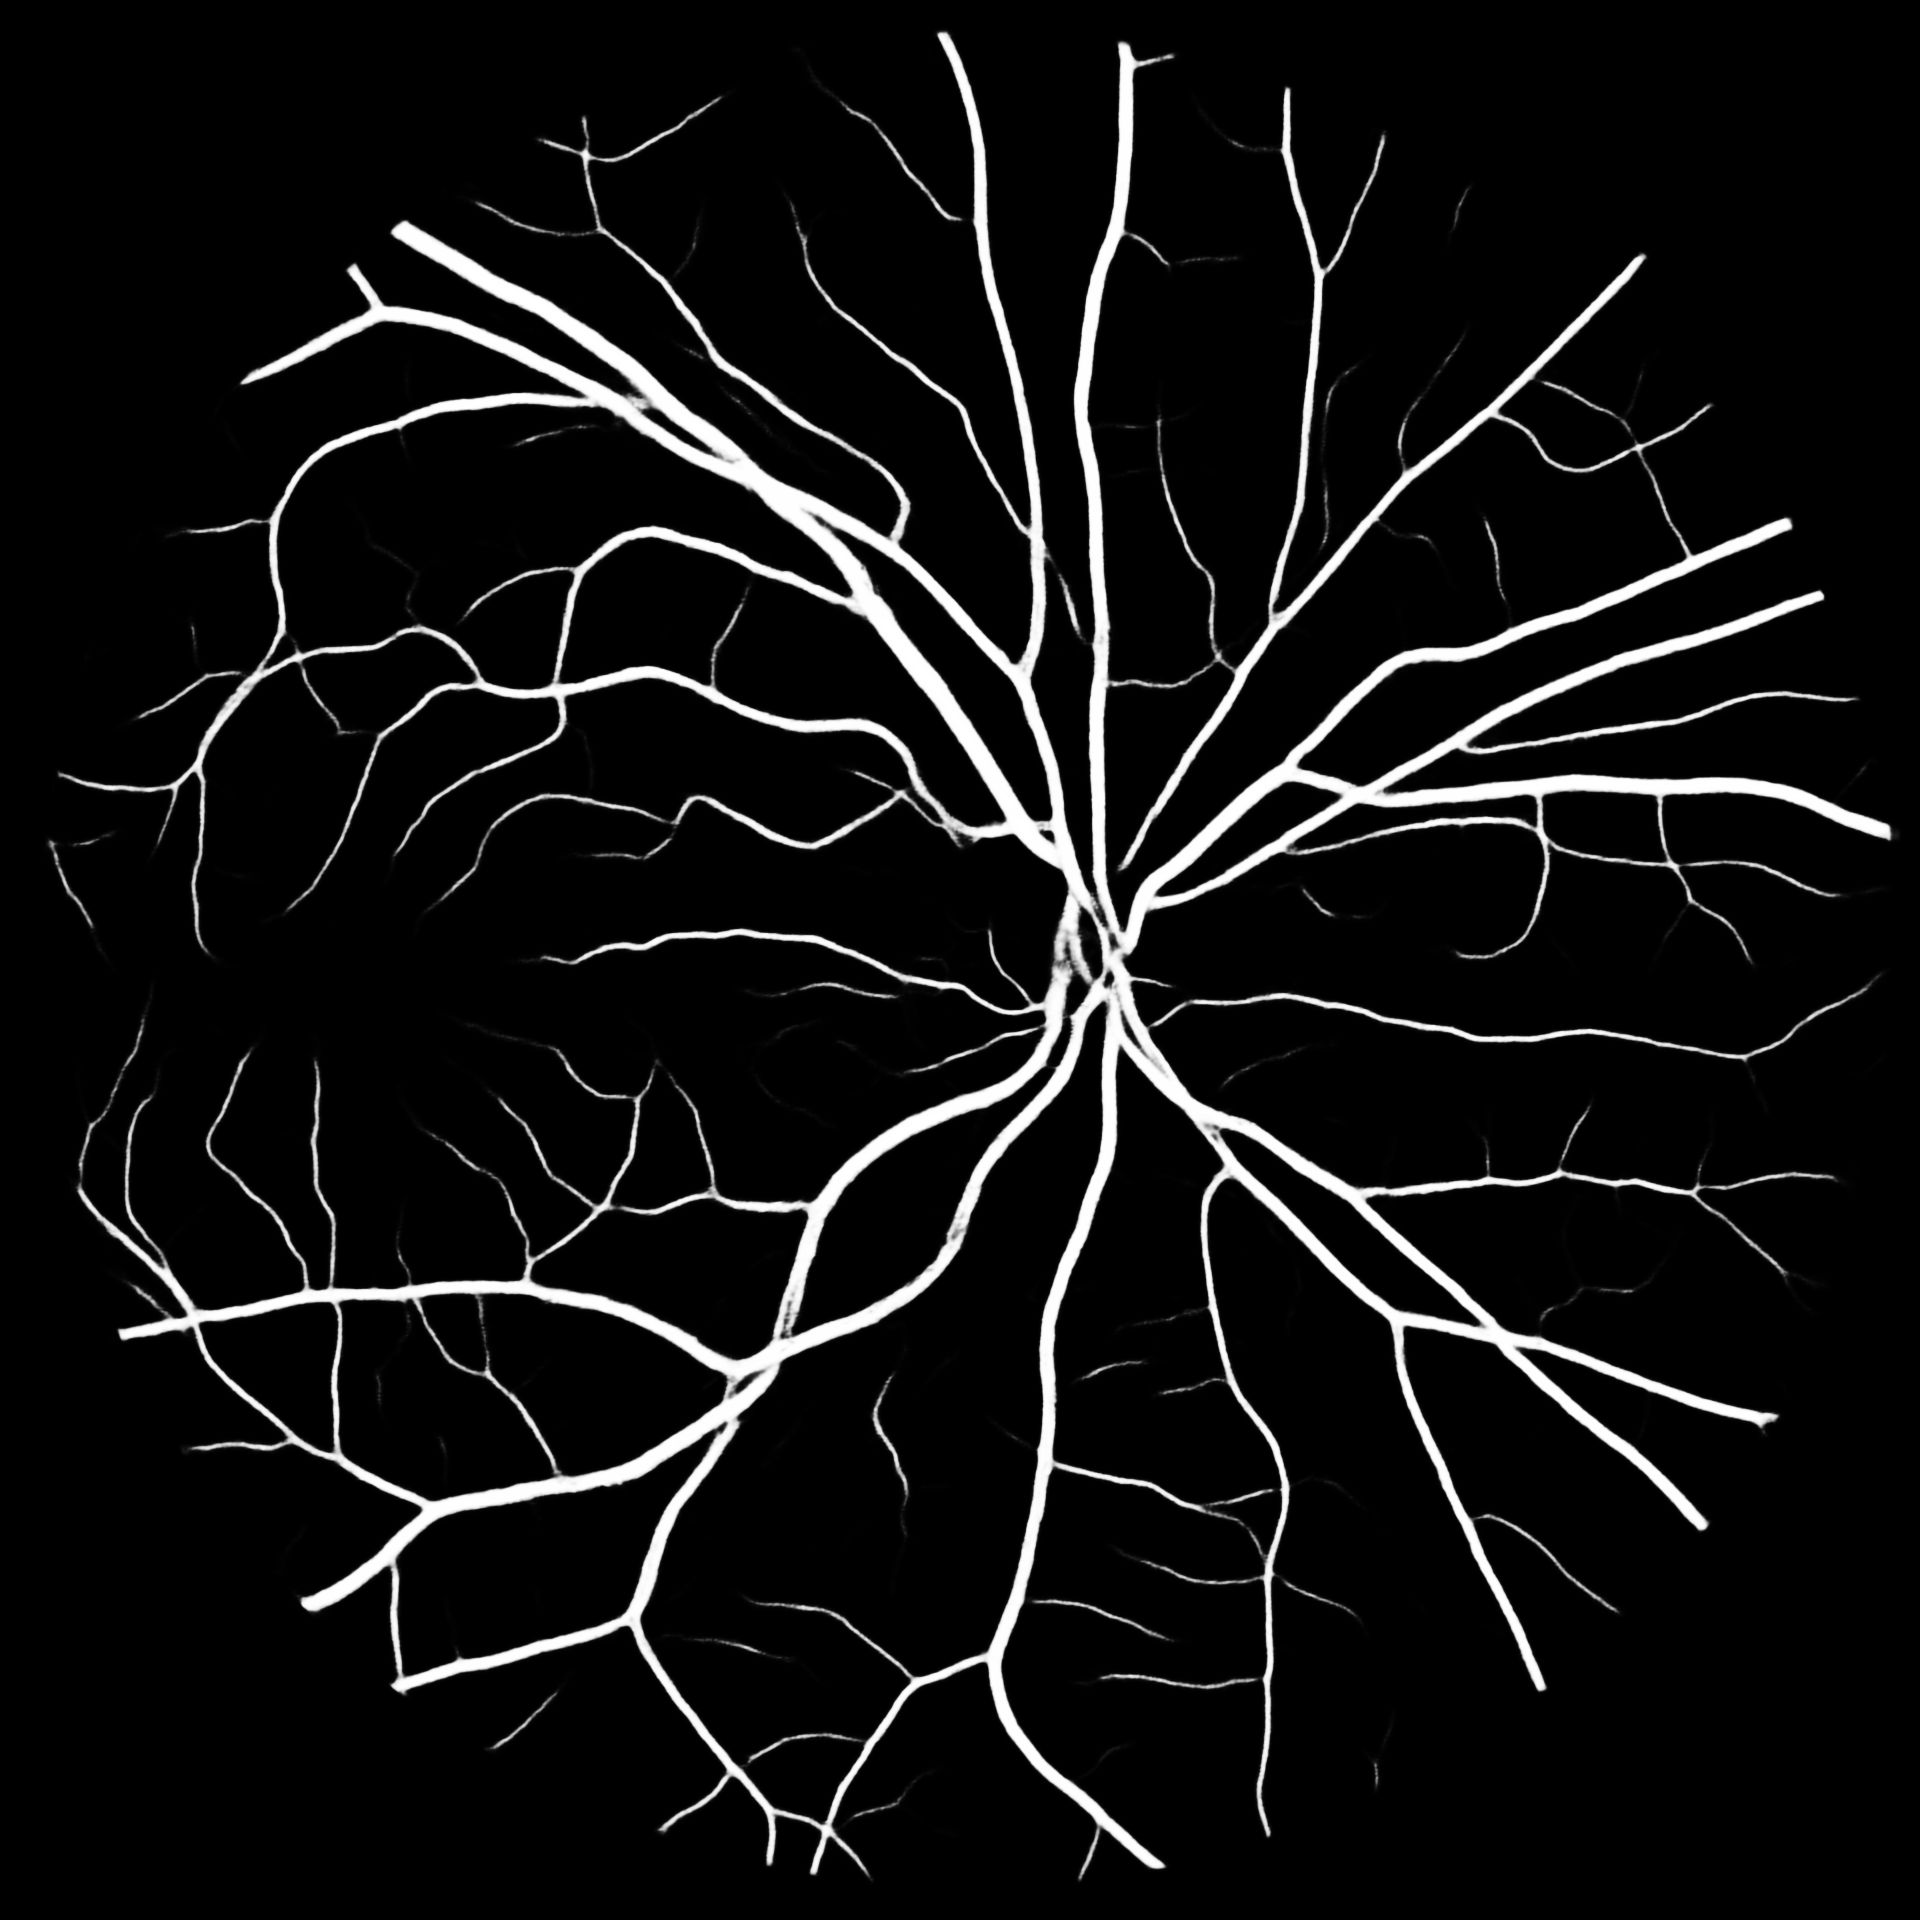

VI Evaluation

To put our results into perspective, Table V compares previous works to our methods. We report the -score for our results together with their standard deviation. Overall M2U-Net and DRIU trained on COVD are competitive, with the best performance on the high-resolution dataset HRF, where a new state-of-the-art F1-score could be reached. Additional metrics such as accuracy, sensitivity, precision and specificity are available in the documentation of our software package. Further, to the available public datasets, we trained M2U-Net on COVD for a private target dataset with a resolution of 1920x1920 for which no ground-truth data is available. The predicted vessel probability maps are displayed in Figure 5. While we can only make subjective statements, we find that the generated probability maps are of good quality, with the majority of main vessels being detected, even in presence of pathologies. An illustration of predicted vessel maps versus ground truths for M2U-Net on HRF is provided in Figure 4.

HRF

COVD

COVD– SSL